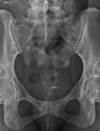

Espondilite anquilosante

Homens jovens, 3 década

Sacroileíte bilateral e simétrica

Coluna: Shiny corners (romanus): erosões nos cantos vertebrais com esclerose reativa;

vértebra quadrada (perda da concavidade anterior); espondilodiscite não infecciosa (lesão de andersson); aparência em bambu (anquilose dos sindesmófitos); sinal da faca (ossificação central - ligamento interespinhoso no rx ap),